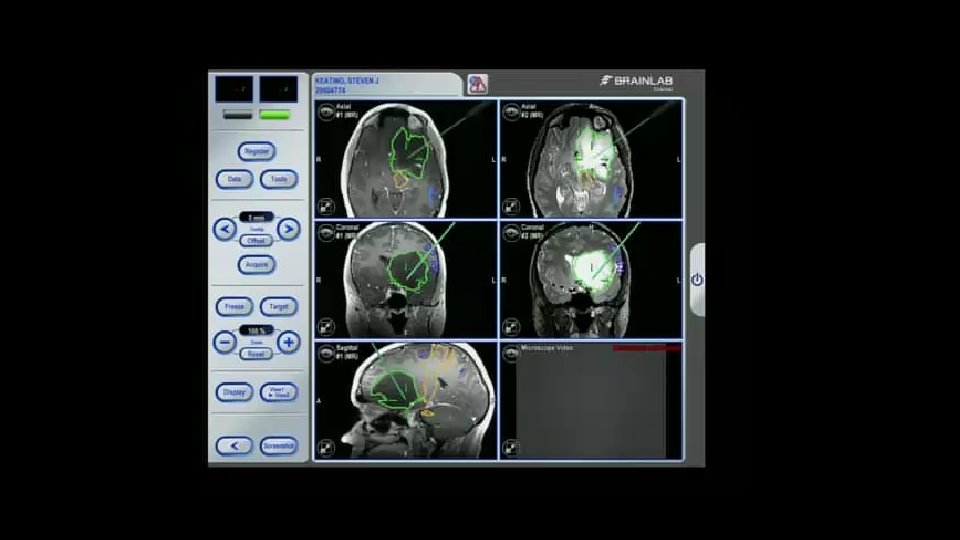

GROSS TOTAL RESECTION (GTR)